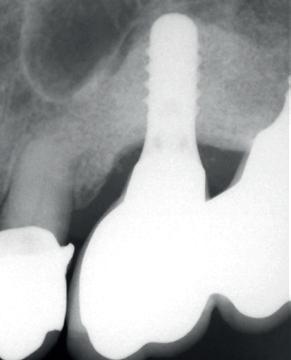

Elektrolytische Reinigung von Zahnimplantaten

Periimplantäre Erkrankungen betreffen immer mehr Patient*innen, da die Zahl der gesetzten Implantate weltweit exponentiell zunimmt.(1) Aus diesem Grund ist in den letzten Jahren auch die Behandlung von biologischen Komplikationen und vor allem die Behandlung einer Periimplantitis stärker in den Fokus gerückt.

Ein wesentlicher, jedoch schwieriger Schritt dabei ist die gründliche Reinigung der Implantatoberfläche. Unter den bisher in der Literatur beschriebenen Methoden im Rahmen der nicht-chirurgischen und chirurgischen Dekontamination erwies sich keine als eindeutig überlegen. (2,3)

Eine mögliche Lösung könnte das 2021 eingeführte Reinigungssystem GalvoSurge® bieten. Bei diesem Verfahren werden Zahnimplantate elektrochemisch dekontaminiert, indem das Implantat mit einer speziellen Reinigungsflüssigkeit besprüht und eine elektrische Kleinstspannung angelegt wird.

Als Folge fließt zwischen dem Sprühkopf (Anode) und dem Implantat (Kathode) Strom und das Wasser in der Elektrolytflüssigkeit (Hydroxy Carbonsäure, Natriumsalz, destilliertes Wasser) wird in Wasserstoff Kationen (H+) und Hydroxid Anionen (OH-) aufgespalten. Die dadurch entstandenen Wasserstoffbläschen sollen den Biofilm aufbrechen und ihn von der Implantatoberfläche ablösen (Abb. 1c).(4, 5) Dieses Verfahren dauert ca. 2 Minuten pro Implantat und ist mit den meisten Implantatsystemen kompatibel.

Aufgrund des jetzigen Sprühkopfdesigns beschränkt sich die Anwendung von GalvoSurge® jedoch auf verschraubte Suprakonstruktionen. Diese müssen vor der elektrolytischen Dekontamination abgenommen werden, damit eine sichere Verbindung zwischen dem GalvoSurge® Sprühkopf und der Implantatinnenverbindung hergestellt werden kann (Abb. 1a,b).

Abbildung 1. Der Sprühkopf (a) wird intraoperativ nach Abnahme der Suprakonstruktion (b) aufgesetzt und die während des Reinigungsprozesses entstehenden Wasserstoffbläschen sollen den Biofilm aufbrechen (c). Fotos © Kristina Bertl

Nach dem Abschrauben der Restauration muss ein Lappen abgehoben werden, um das periimplantäre Entzündungsgewebe gründlich entfernen zu können, da die reinigende Wirkung von GalvoSurge® sich nur da entfalten kann, wo die Spüllösung Kontakt zur Implantatoberfläche hat.

Anschließend kann der operative Eingriff je nach Defektkonfiguration fortgesetzt werden – resektiv oder rekonstruktiv; mehr dazu gab es bereits in unserem letzten Telegramm YOUNGSTERS TELEGRAMM 01-2024!

Zusammengefasst erfordert dieses Implantatreinigungssystem zur Zeit einen verschraubten Zahnersatz in Kombination mit einem chirurgischen Eingriff, was doch zahlreiche Periimplantitisfälle ausschließt. Daher wäre sowohl ein modifiziertes Sprühkopfdesign für zementierte Suprakonstruktionen als auch der Einsatz der elektrolytischen Reinigung im Rahmen einer nicht-chirurgischen Therapie interessant. Das Gleiche gilt für unabhängige klinische Studien, die die Wirkung dieses neuen Verfahrens weiter untersuchen, da die aktuelle Studienlage auf diesem Gebiet noch einige Fragen offenlässt.